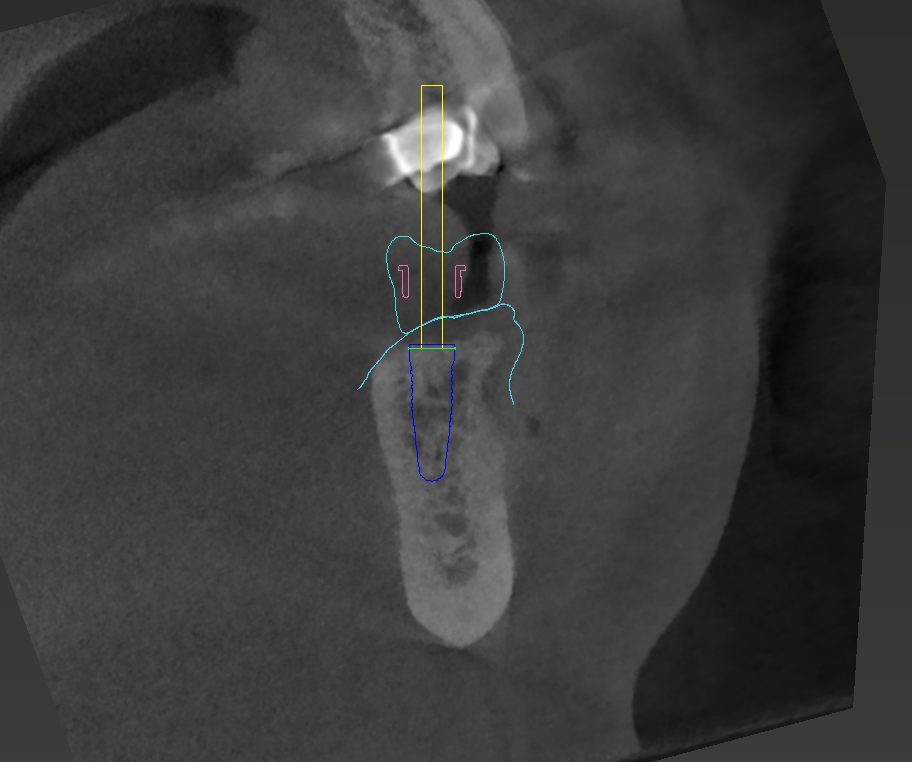

Eine vorrausschauende und präzise Planung in der Implantologie ist der Schlüssel, um für die anschließende Prothetik ein planbares und erfolgreiches Ergebnis zu erzielen.

Wir nutzen 3D-navigierte Planungsprogramme

• CoDiagnostiX

• Exoplan

Durch die Vielzahl an Möglichkeiten, die diese Programme bieten, stellen wir vollnavigierte Bohr- und Pilotbohrschablonen sowie einfache OP-Schablonen her.